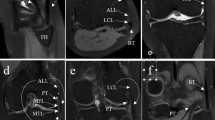

The axis of rotation had a maximum change in orientation between the intact scenario and the others of 20.6° (α angle Fig. 5b) on the YZ plane, 13.7° (β angle Fig. 5a) on the XY plane and 4.1° (γ angle Fig. 5c) on the XZ plane. A progressive displacement of the axis up to 4.13 mm in postero-cranial direction was observed (Fig. 5d). Table 3 shows the single components of each axis for orientation and plane intersection.

Changes in the axis of rotation for the different scenarios. Each scenario is the average of 4 repetitions. Changes in orientation of the axis of rotation for the ZY plane (a), XY (b) and XZ (c). (d) Differences in the intersection with the ZY plane passing through the centre of the articular surface of the talus; Scenario 1: Intact; Scenario 2: section of ATFL; Scenario 3: section of ATFL and CFL; Scenario 4: section of ATFL, CFL and PTFL; α angle: scenario 1 vs scenario 4; β angle: scenario 1 vs scenario 2; γ angle: scenario 1 vs scenario 4.